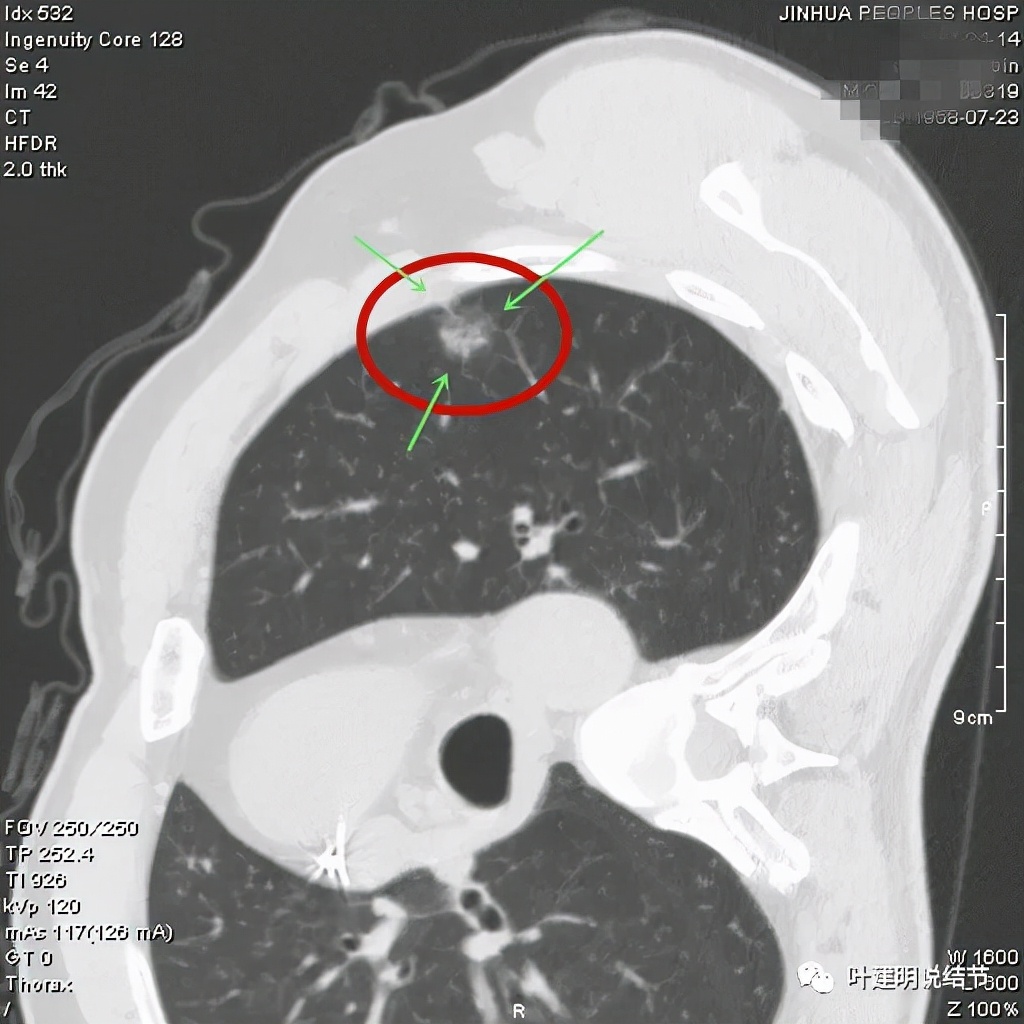

病灶瘤肺边界清,密度偏低,有点散,但有微小血管进入(桔色箭头)

病灶整体密度较低,但轮廓较清,内部密度不大均匀,显得杂乱

不均质的偏低密度磨玻璃结节,轮廓清